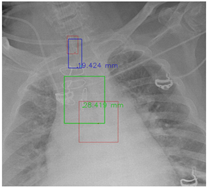

4.5.8. Visualization

In this part, the red bboxes and points denote the GT ETT/bifurcation bboxes and the position of GT ETT tip/Carina, respectively. The blue bbox and point are the predicted ETT bbox and ETT tip, respectively. The green bbox and point are the predicted bifurcation and Carina, respectively. The light blue point is the position of the ETT tip produced by the mask branch. In the Table 23, the first row demonstrates the good results, the second row shows the medium results, and the third row presents the bad results. We noticed that if an image had a clear location of the ETT tip and the Carina, the performance would be better. Moreover, the life-supporting device might blur the location of the ETT tip and the shadow of the heart might occlude the position of the Carina as shown in the medium case. Apart from the problems mentioned above, the angle of the CXR might also degrade the performance of the proposed method, as shown in the worse results when it is applied.

Table 23. The visualization results.

Good Diagnostics 12 01913 i001 Diagnostics 12 01913 i002

Medium Diagnostics 12 01913 i003 Diagnostics 12 01913 i004

Worse Diagnostics 12 01913 i005 Diagnostics 12 01913 i006